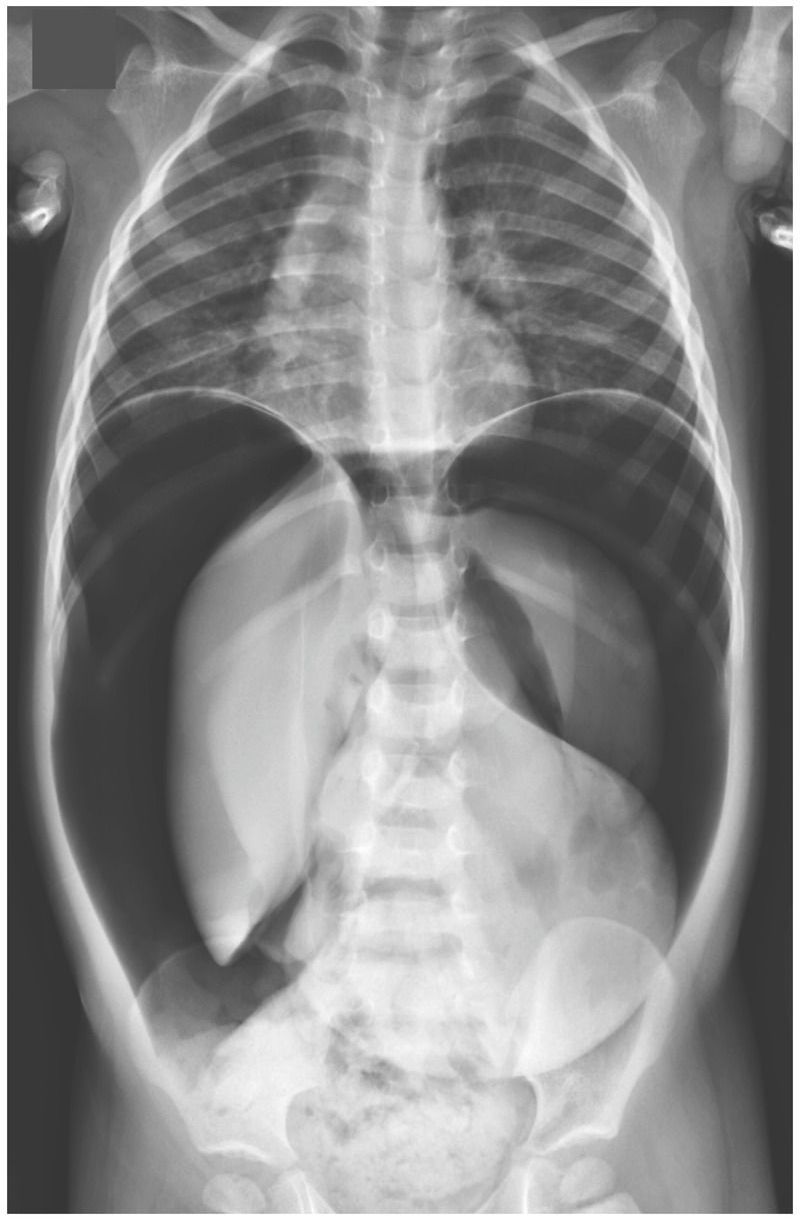

A two-and-a-half-year-old boy was brought to the emergency department after he had a seizure during a febrile upper respiratory illness. An adult who witnessed the seizure was concerned that the boy had stopped breathing and initiated chest compressions and rescue breathing. The boy regained consciousness after approximately 1 minute. On physical examination, he was awake and interactive, and a neurologic examination showed no deficits. He appeared uncomfortable, and his abdomen was distended, tympanitic, and tender. Radiography of the abdomen showed pneumoperitoneum. No rib fractures were noted. Exploratory laparoscopy revealed a perforation on the posterior wall of the stomach, without intraperitoneal fluid or other small or large bowel abnormalities. The gastric rupture was thought to have been caused by barotrauma from acute gastric distention during the resuscitation attempt. The perforation was repaired surgically. The patient remained in the hospital for 3 days, and no additional gastrointestinal issues or seizures were observed. He recovered uneventfully from surgery and the upper respiratory illness. At a follow-up visit 6 months later, he was growing and developing well.